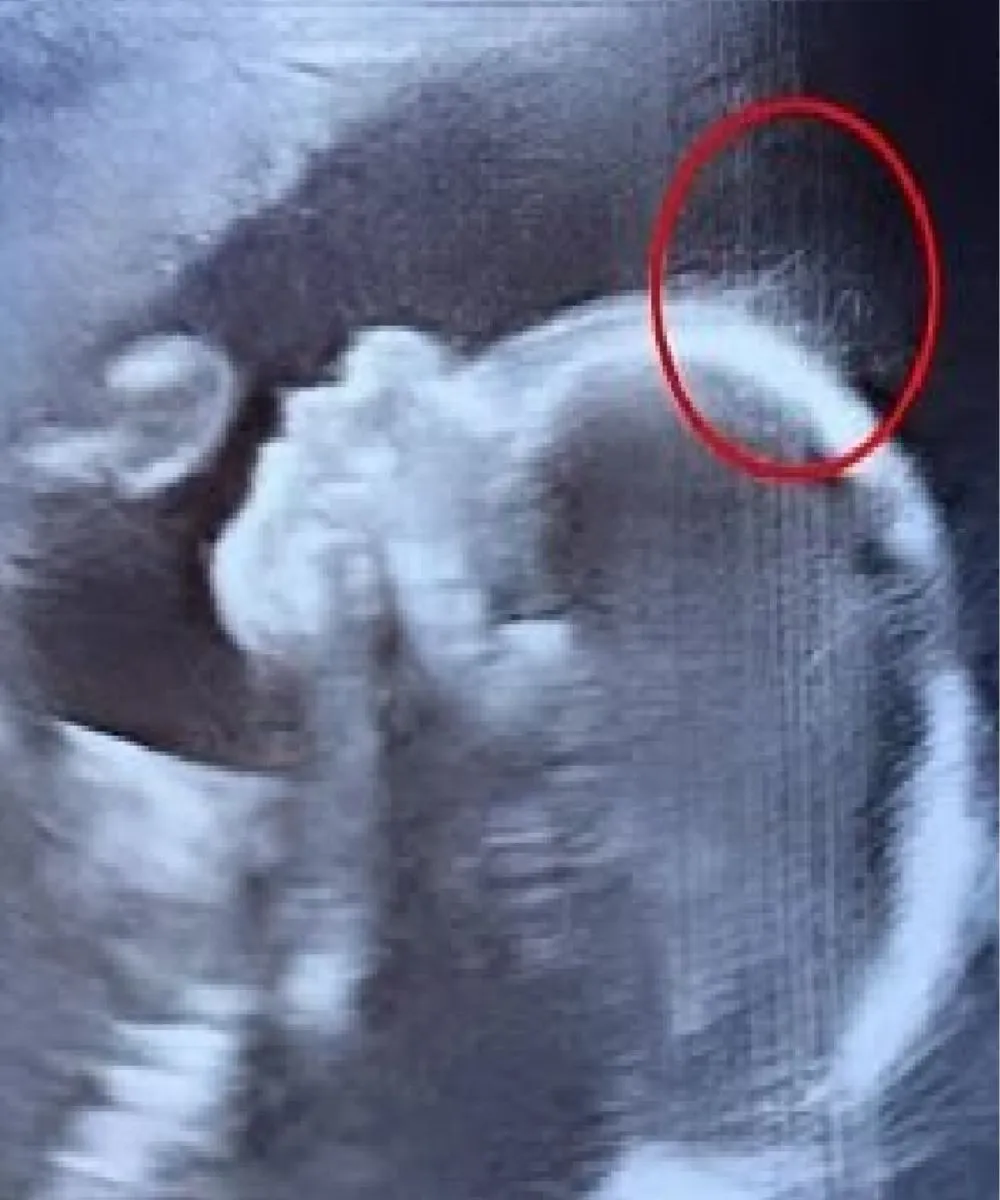

While displaying the ultrasound, the sonographer witnessed the monitor all puzzled, but then she smiled and said, “Wait a minute. Is that hair?” One of the doctors approached closer and said jokingly, “Looks like you’ve got a little rock star in there — she might just skip the baby baldness entirely!”

Indeed, the ultrasound performed wispy strands swaying underwater like seaweed.

What was noticeable was that Ivy’s hair was clear during the scan, and that it was awesome long for a newborn baby.